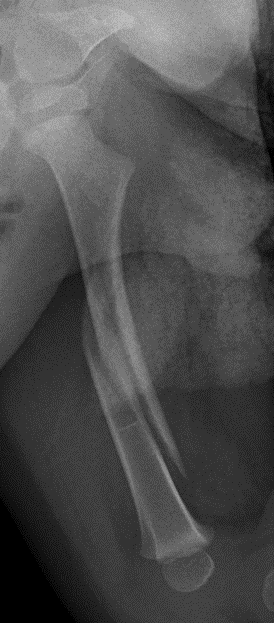

Flexible nails / Titantium Elastic Nails

Indications

Length stable fractures i.e simple transverse, short oblique

Midshaft fractures

Maximum weight up to 50 kg / 12 years old

Complications

- 234 femur fractures treated with flexible nails

- age > 11 and weight > 50 associated with poorer outcomes

- age < 11 good outcome 72%, age > 11 good outcome 55%

- leg length discrepancy and angulation associated with poorer outcomes

Narayanan et a. J Paediatr Orthop 2004

- reported on 79 patients treated with flexible nails

- pain and irritation at insertion site common

- malunion / loss of reduction associated with nails of differing diameters and increased comminution